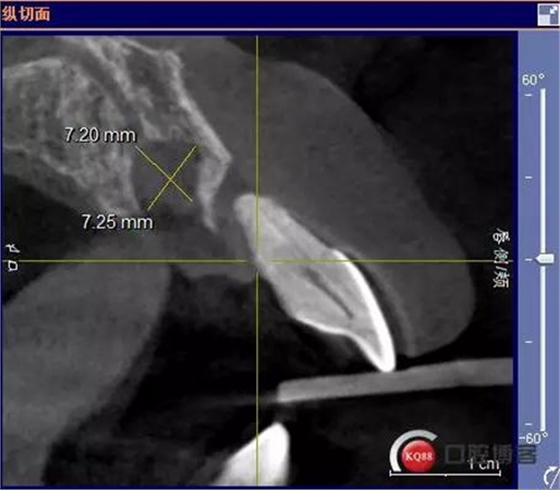

患者:王XX 年齡:42 上前牙松動數(shù)年,從未做過任何處理,今來院就診;檢查:CBCT示上前牙區(qū)顎側(cè)一大小約7x7mm囊腫;治療計劃:即刻種植同期摘除囊腫

術前CBCT